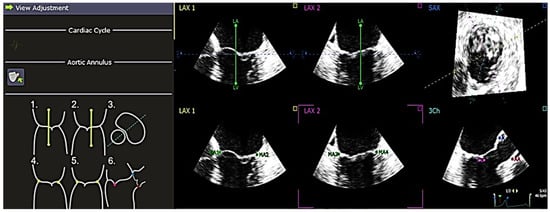

2.2. QLAB 13 Software Analysis

The software used to analyze the 4D echocardiography data was QLAB 13, an experimental, unreleased software developed by PHILIPS and TomTec, which was approved by the FDA on 18 June 2019. A set of Q-apps analysis tools equipped in the software could be selected for the quantitative analysis of echocardiographic data. These tools included 4D Mitral Valve Assessment (MVA), Mitral Valve Navigation (MVN), General Imaging 3DQ (GI3DQ), etc. The MVA feature was used to perform echo analysis, allowing the extraction of essential variables for the study. The positions of the mitral valve annulus and leaflets were automatically generated by the software, outlined using “points” and “lines” superimposed on the approximated margins of the mitral valve, as shown in Figure 1. These “points” and “lines” could be adjusted manually to gain a more accurate approximation of the actual position of the mitral valve using the next three stages of review, namely, view adjustment, static model (Figure 2), and dynamic model (Figure 3) reviews.

Figure 2. “Static Model Review” shows a static model of the mitral valve generated using QLAB 13R software showing the anterior and posterior leaflets. The lines are adjusted according to the reference found at the left under the “Static Model Review”. There are two views provided, which are annulus and coaptation views. For the two views, it is important to ensure that the line is aligned with the mitral valve. A1, A2, A3 = anterior leaflet, P1, P2, P3 = posterior leaflet, SAX = short axis.